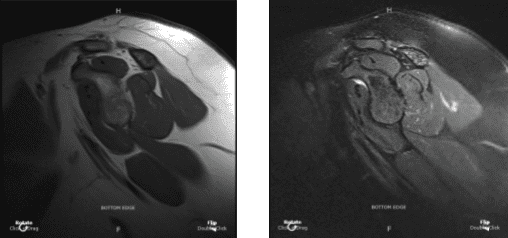

MRI Right shoulder non-contrast